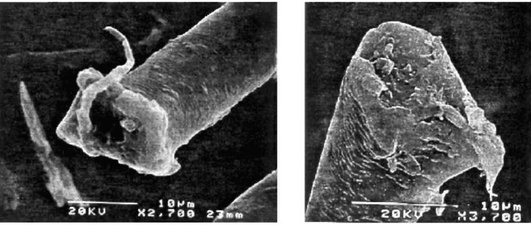

Характер воздействия экзогенных факторов на организм зависит от размера, формы, площади поверхности, заряда, химических свойств, растворимости, степени агломерации вдыхаемых частиц. Чем меньше диаметр частиц, тем больше их общая поверхность. Так, общая поверхность 1 мг вещества при диаметре частиц 10 мкм (1012 частиц) составляет 270 м2 , а при диаметре 10 нм (1021 частиц) - 270 000 м2 , что обусловливает большую поражающую активность наночастиц. Кроме того, высокое соотношение сторон (отношение длины частицы к ее диаметру) у нанотрубок значительно повышает повреждающее действие частиц, приводя к незавершенному фагоцитозу и постоянной активации альвеолярных макрофагов. Повреждающее действие нейлонового флока обусловлено игольчатыми, линейными структурами на концах нейлоновых волокон, образующимися при их разрезании (рис. 2.24).

Патогномоничным для заболеваний легких от аэрозолей твердых металлов («кобальтовое легкое») является гигантоклеточная интерстициальная пневмония (гигантские многоядерные клетки с чертами каннибализма - «клетка в клетке»), но могут выявляться изменения, характерные для ДИП (десквамация клеток в альвеолы), лимфоплазмоцитарная инфильтрация и различная степень интерстициального, преимущественно центрилобулярного, фиброза (рис. 2.27, см. цв. вклейку, табл. 2.11). Так, при воздействии вольфрама и некоторых лекарственных препаратов могут выявляться соответственно причудливой формы пенистые альвеолярные макрофаги (Forni A., 1994; Lessnau K.-D. et al., 2019).

Бронхологические методы исследования. Фибробронхоскопия выявляет наличие диффузного катарального эндобронхита или атрофические изменения слизистой оболочки бронхов как следствие перенесенного токсического бронхита. Отмечается как нейтрофилез, так и лимфоцитоз ЖБАЛ. При ингаляционных лихорадках в ЖБАЛ увеличивается число нейтрофилов и цитокинов (Ahsan S.A. et al., 2009; Greenberg M.I. et al., 2015). Прогрессирование пневмофиброза сопровождается увеличением числа нейтрофилов в ЖБАЛ. Цитологический состав ЖБАЛ позволяет уточнить характер экспозиционного фактора. Повышение числа лимфоцитов и значительное повышение отношения CD4/CD8 клеток в ЖБАЛ характерно для бериллиоза (Clinical guideline for the diagnosis of Berillium, 2015). При ЭТА от аэрозолей твердых металлов («кобальтовое легкое») в ЖБАЛ повышается число всех видов клеток: альвеолярных макрофагов, лимфоцитов, нейтрофилов, эозинофилов и даже выявляются тучные клетки. При воздействии цинка, магния, кадмия, никеля и ванадия в ЖБАЛ повышается число нейтрофилов. В ряде случаев в ЖБАЛ можно выявить изменения альвеолярных макрофагов, характерные для воздействия определенных веществ: вольфрама (причудливые макрофаги), лекарственных препаратов (пенистые макрофаги), кобальта (причудливые гигантские многоядерные клетки с признаками каннибализма, так называемые клетка в клетке) (Meyer K.C. et al., 2012; Mizutani R.F. et al., 2016). Ядерно-активный анализ ЖБАЛ помогает уточнить тип металла.